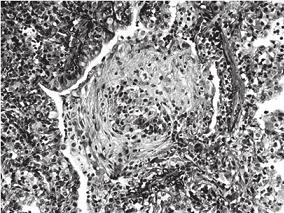

1小时条评论患儿,男性,1岁7个月,以咳嗽、气喘2个多月为主诉于2010年11月3日入住福建省立医院儿内科。 患儿2个多月来反复咳喘,剧烈时烦吵不安,喝水呛咳,在多家三甲医院给予头孢类药物、糖皮质激素、雾化等治疗,患儿咳喘时轻时重,外院肺部CT检查提示双肺呈磨玻璃样改变,...